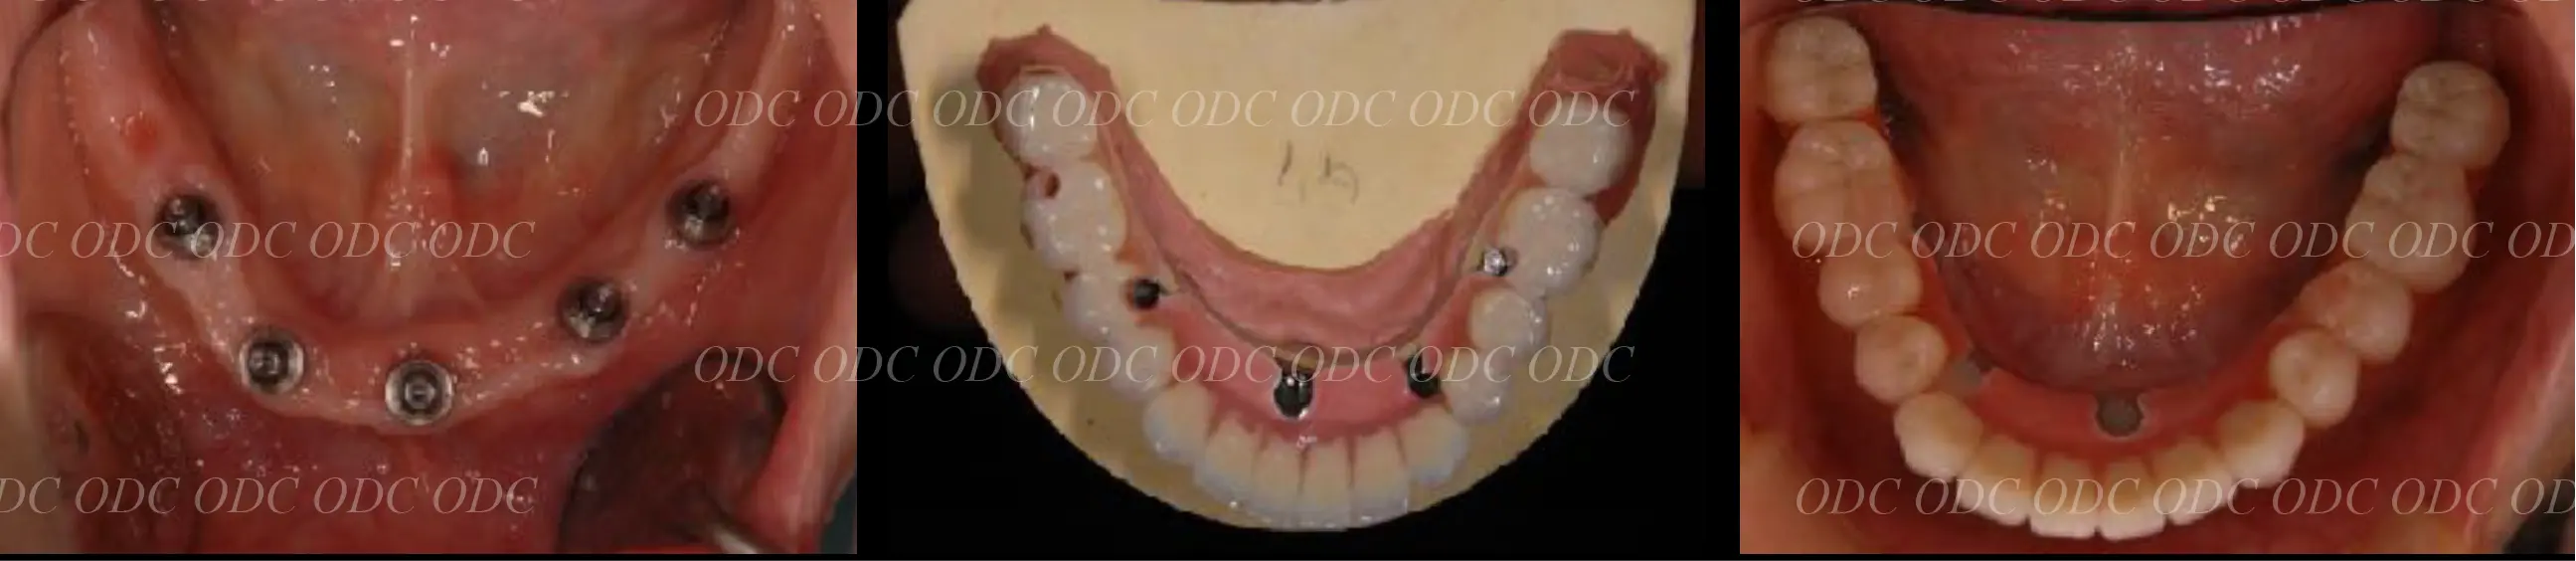

インプラントオーバーデンチャー症例

インプラントオーバーデンチャーとは、インプラントで入れ歯を支える方法です。

清掃がしやすいなどのメリットがあります。

また、多くの入れ歯の方が気持ち悪いと言われる上顎の内側の部分を大きく開けることができます。

上顎はCADCAMで作製されたバーを使用し、ロケーターとクリップを併用しています。

下顎は、ロケーターと呼ばれるアタッチメントで入れ歯が安定するようにしています。

インプラントオーバーデンチャーは、できれば3本以上のインプラントを使用すると安定しやすくなります。

2024年

治療終了後約13年経過しますが、上の入れ歯の前歯部分が破折してきて修理しています。

インプラントオーバーデンチャーは、掃除がしやすいなどのメリットはありますが、固定式のタイプと比較して摩耗しやすく、割れやすい等のトラブルは多くなることを覚えておいた方がいいでしょう。